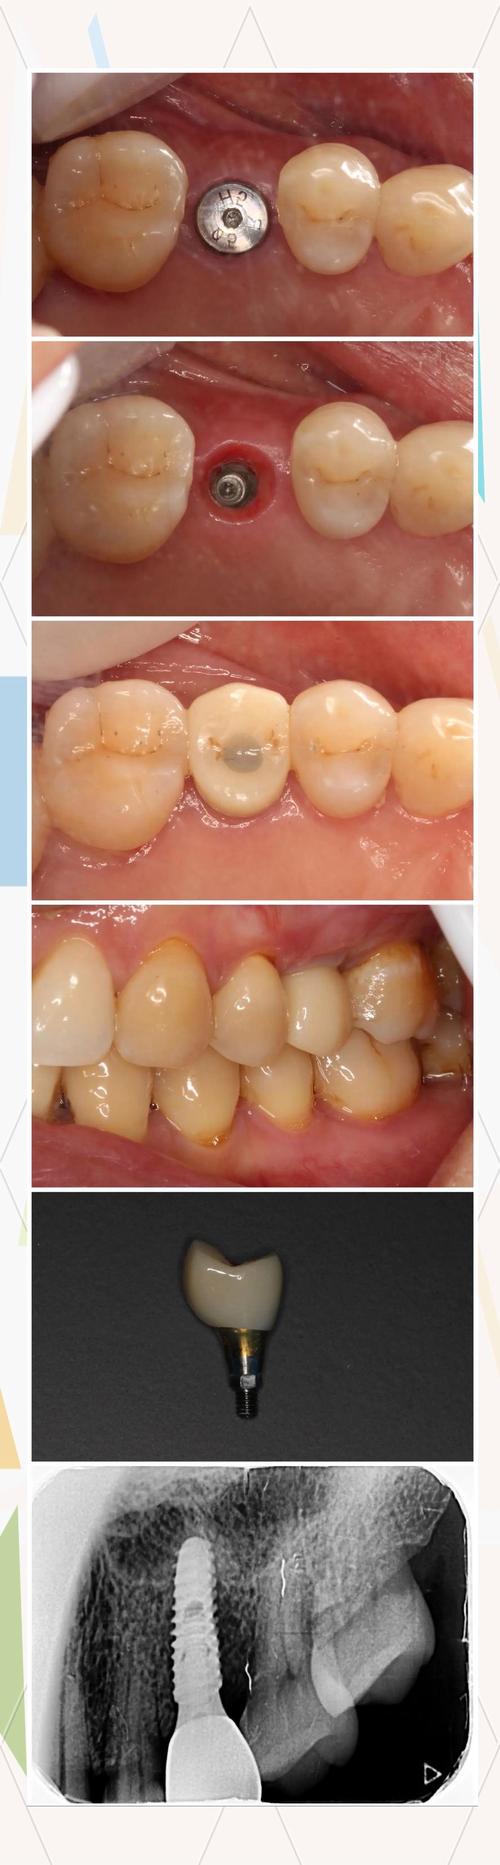

种植体植入术

在局部麻醉下,医生切开牙龈,逐级备洞后将种植体(类似人工牙根)植入牙槽骨内,传统手术需切开翻瓣,而微创种植仅需3-4mm小切口,出血少、恢复快,手术时间约为30分钟-1小时/颗,复杂病例可能更长。

基台安装与牙冠修复

骨结合完成后,安装基台(连接种植体与牙冠的部分),然后取模制作牙冠,牙冠材料有全瓷、烤瓷、金属等,全瓷牙冠因美观、生物相容性好,成为主流选择,价格约2000-8000元/颗。